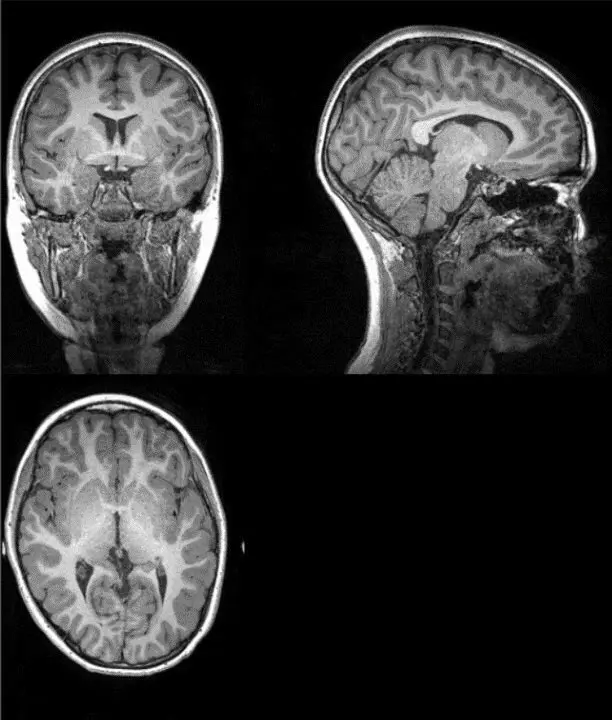

Archivo - Ejemplo de imagen original de la resonancia magnética a partir de la cual investigadores de la UGR han extraído la cantidad total de materia gris, materia blanca, y cantidad total cerebral

Los investigadores analizaron tomografías computarizadas en 120 pacientes neurológicos, incluidos 58 con COVID-19 agudo y 62 sin COVID-19, emparejados por edad, sexo y enfermedad. El trabajo se realizó conjuntamente con Enrico Premi y sus colegas de la Universidad de Brescia (Italia), que proporcionaron los datos para el estudio. Utilizaron un análisis de morfometría basado en la fuente, que aumenta la potencia estadística de los estudios con un tamaño de muestra moderado.